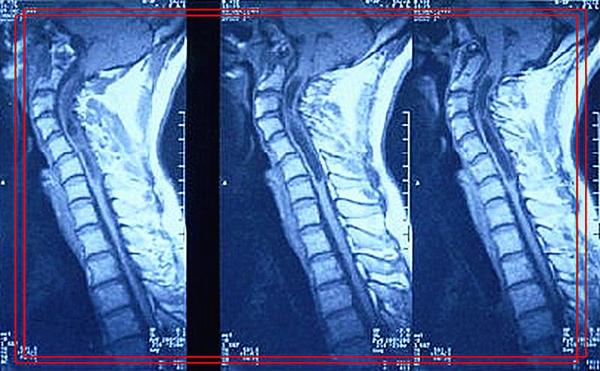

影像学资料

影像学解读

颈椎MRI显示:小脑扁桃体下疝入颈椎管,颈2-7节段脊髓中央管扩大。

确诊:小脑扁桃体下疝畸形伴脊髓空洞